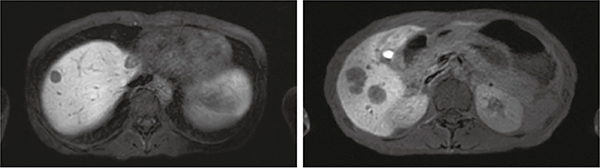

図7は,RADAR-RAPIDによるGd-EOB-DTPA臨床画像例である。自由呼吸下におけるRAPIDファクタ2倍,撮像時間3分50秒の画像であるが,腹壁のモーションアーチファクトが低減された良好な画像が得られている。

図7 RADAR-RAPIDによるGd-EOB-DTPA臨床画像例

T1強調画像〔撮像時間:3分50秒,RADAR-RAPID(自由呼吸下)〕